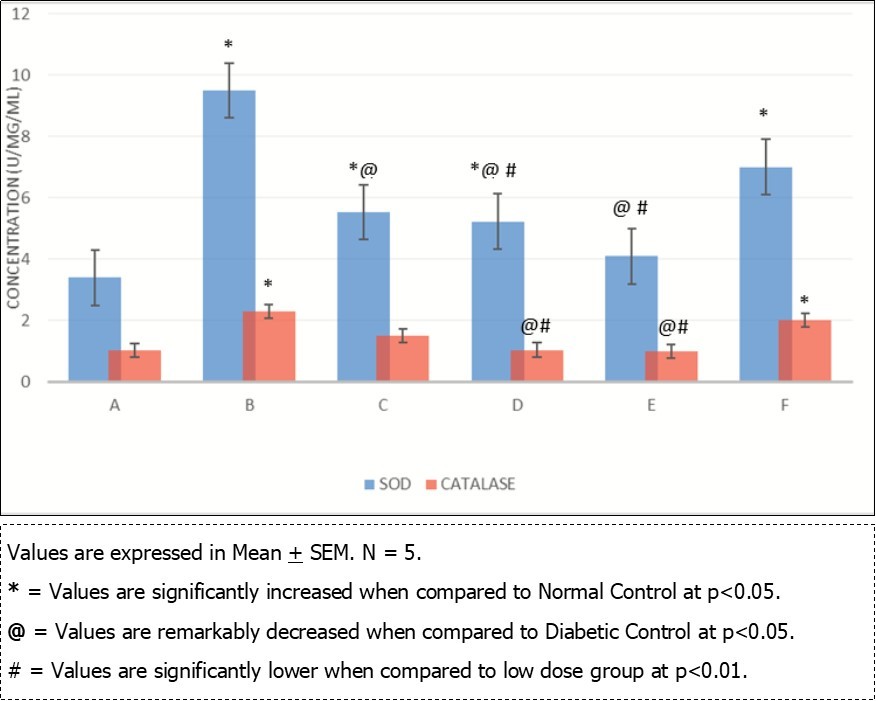

Local Nigerian men have been using AuriculariaPolytricha as a treatment for sexual dysfunction without supporting evidence from scientific experiments. This study was to investigate the effect of ethanolic extract of A. Polytricha on testicular DNA expression and some oxidative stress markers using STZ-Induced diabetic rats as a model. The experiment included six groups, Group A (Normal Control, treated with normal saline), Group B (treated with 65mg/kg.bw of STZ), Groups C, D, and E (treated with 250mg/kg.bw, 500mg/kg.bw, 1000mg/kg.bw AP after inducing diabetics), and Group F (treated with 40mg/kg.bw metformin after inducing diabetics). The experiment lasted for 35 days. After termination of the experiment, Fuelgen nuclear reaction was used for DNA demonstration to assess testicular DNA distribution while serum Superoxide Dimutase (SOD), Catalase and Melondialdehyde where evaluated using reagent based antioxidant enzyme assay. Results reveals that SOD and Melondialdehyde activities were remarkably (p<0.05) higher in diabetic control animals when compared with the normal control group. Values in Groups C, D and F that were administered with 250, 500mg/kg.bw A. polytricha and metformin respectively were also significantly (p<0.05) increased when compared with the normal control group. However, diabetic animals placed on 1000mg/kg.bw A. polytrichadid not show any statistical significance in comparison with normal control group but was remarkably (p<0.01) decreased when compared to the diabetic group that received low dose A. polytricha, an indication that the reversal is dose dependent. Catalase concentration in diabetic control animals was remarkably (p<0.05) higher when compared to the normal control but was not significantly (p<0.05) different in groups D (DM+500mg/kg.bw A. polytricha) and E (DM+1000mg/kg.bw A. polytricha) when compared with the normal control group. Diabetic control animals showed reduced magenta colour intensity of DNA and increased clustering and cross linking of DNA strands when compared with the normal control. However the degree of cross link in DNA strands was reduced in the diabetic animals placed on 1000mg/kg.bw A. polytrichawhen compared with the diabetic control group. Reversal in DNA damage and values of serum oxidative stress markers following administration of graded doses of A. polytricha could be attributed to essential phytochemical and therapeutic constituents in A. polytricha like polyphenol and flavonoid which can be found useful in prevention and treatment of diabetes induced testicular dysfunction. In summary, AP can contribute to a reversal in DNA damage and levels of serum oxidative stress markers in treating diabetes-induced testicular dysfunction.

Oxidative stress markers (SOD, catalase and Melondialdehyde) activities of different experimental animals. Figure 1, Figure 2. Results from Fuelgen DNA demonstration is shown in Figure 3, Figure 4, Figure 5, Figure 6, Figure 7, Figure 8.

Figure 1.Comparison of Supperoxide Dimutase (SOD) and Catalase in the different experimental groups.

Results obtained from analysis of serum oxidative stress markers shows that both SOD and Melondialdehyde activities were remarkably (p<0.05) higher in diabetic control animals when compared with the normal control group. Values in Groups C, D and F that were administered with 250, 500mg/kg.bw A. polytricha and metformin respectively were also significantly (p<0.05) increased when compared with the normal control group. However, diabetic animals placed on 1000mg/kg.bw A. polytrichadid not show any statistical significance in comparison with normal control group but was remarkably (p<0.01) decreased when compared to the diabetic group that received low dose A. polytricha, an indication that the reversal is dose dependent.

Catalase concentration in diabetic control animals was remarkably (p<0.05) higher when compared to the normal control but was not significantly (p<0.05) different in groups D (DM+500mg/kg.bw A. polytricha) and E (DM+1000mg/kg.bw A. polytricha)when compared with the normal control group. In a similar study, Mallidis et al., (2011) noted that melondialdehyde and caspase-3 activities were significantly higher, whereas SOD and GPx enzymatic activities were remarkably lower in diabetic rats when compared with normal control group. Three weeks administration of A. polytricha revealed a reduction in the values of melondialdehyde concentration in diabetic animal models. The decrease in these values was done in a dose-dependent manner. This findings are consistent with the work done by Mohasseb et al., 2011; Agbaje et al., 2007. They documented that antioxidant supplementation play a role on testicular germ cell apotosis of STZ-induced diabetic rat and can restore both testicular and systemic enzymatic activities of melondialdehyde and caspase-3. A. polytricha antioxidant property is achieved because of the presence of naturally occurring antioxidants like tocopherol, acobic acid, and total phenols 16. Sun et al., (2010) also reported that uronic acid has been fractionized from fruiting body of A. polytricha and that the higher the uronic acid content, the more effective the antioxidant activity of the polysaccharide. A. polytricha also has high phenolic and flavonoid content; glutathione reductase and superoxide dimutse activity 18. Chen et al. (2015) demonstrated that A. polytricha polysaccharides improved significantly, total antioxidant capacity and lipoprotein lipase activity in mice but was found to reduce melondialdehyde levels and arteriosclerosis index in rats and he attributed the strong antioxidant status to the phenolic compound in A. polytricha.